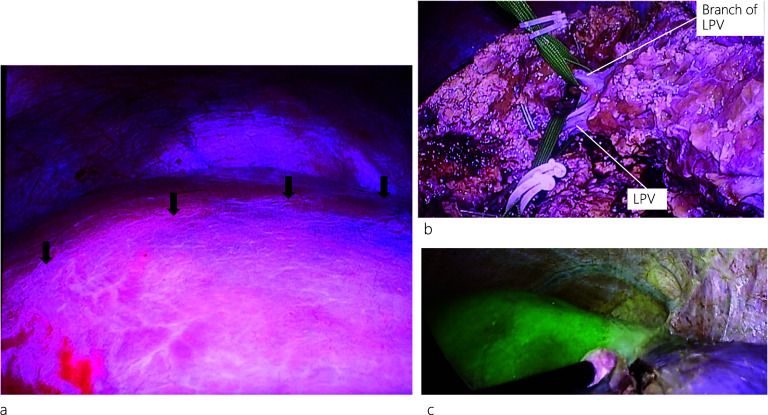

During the operation, when we first encircled and clamped the left Glisson’s sheath, no demarcation lines appeared. Under intraoperative US guidance, indigo carmine (10 mg) was injected into the LPV above the MHV, and a temporary demarcation line appeared (Fig. 4a). Subsequently, the hepatic parenchyma was transected along the demarcation line and encircled the LPV. After clamping the LPV and injecting indocyanine green (ICG: 2.5 mg) through a peripheral vein, negative staining using ICG fluorescence real-time imaging showed hepatic perfusion, and the demarcation line was clearly visible (Fig. 4b, c). Transection of the liver parenchyma was continued, and left hepatectomy was completed. Intraoperative frozen section histopathology of the cut end of the left hepatic bile duct was negative for malignancy. The operation time was 413 min, and blood loss was 83 mL. Pathological reports showed only inflammation of the bile ducts, without any malignancy (Fig. 5a–c), while postoperative 3D CT images showed preserved MHV and right PV. The patient developed an intraabdominal abscess, for which CT-guided drainage was performed on postoperative day (POD) 13. After successful treatment, the drain was removed, and the patient was discharged on POD 28.

It is difficult to determine the demarcation line when performing left hepatectomy in patients with APB. In this situation, the only option is to split the liver parenchyma along the Rex–Cantlie line and separate the PV from the anterior section. Besides our limited experience with this technique, we initially attempted PV puncture by injecting indigo carmine (10 mg) into the LPV above the MHV under US guidance to visualize the demarcation line. However, only a temporary demarcation line appeared (Fig. 4a). The hepatic parenchyma was transected along this temporary demarcation line, and the LPV was dissected and encircled. We then injected ICG (2.5 mg) into the peripheral vein, and after clamping the LPV, we could precisely see the well-established demarcation line (Fig. 4c) using ICG fluorescence real-time imaging and completed the left hepatectomy. However, owing to the complexity of liver resection, the hepatic cut surface was not smooth. This could have promoted the formation of abscesses at the cut margins and eventually lead to a postoperative intraabdominal abscess, for which the patient was successfully treated with CT-guided drainage and antibiotics.

ICG fluorescence imaging has been used for intraoperative identification of hepatic tumors and segmental boundaries during laparoscopic hepatectomy, particularly for anatomical resection [ref. 14, ref. 15]. Recently, this technique has become common during laparoscopic hepatectomies because fluorescence images can allow surgeons to identify the segmental boundaries of the hepatic parenchyma with or without blood perfusion and thus guide surgeons to complete anatomic resections laparoscopically [ref. 16]. Although the histopathological report revealed this case as a benign disease, ICG fluorescence real-time imaging was used preoperatively, and we planned to perform a laparoscopic anatomical liver resection based on a strong suspicion of intrahepatic cholangiocarcinoma due to the impacted IHBD stones. Therefore, this real-time intraoperative imaging technique might be useful for patients with APB requiring hepatectomy by facilitating the visualization of the demarcation line and consequently aiding in liver parenchyma resection. Although the assessment of hepatic perfusion by fluorescence imaging following the intravenous injection of ICG cannot be used repeatedly, this modality can allow surgeons to perform safe and accurate laparoscopic hepatectomies.